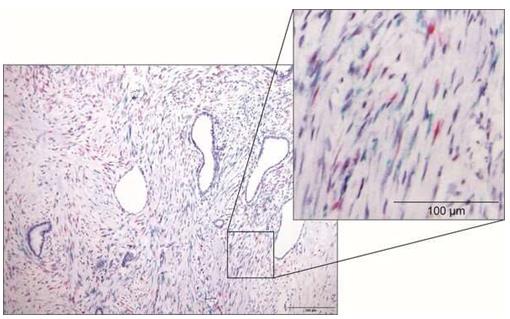

名古屋大學:已經確定胰腺癌中存在抑制癌細胞的細胞

原位雜交數據顯示人胰腺癌中Meflin陽性成纖維細胞(品紅色)和-陰性成纖維細胞(綠色)的浸潤。來源:水谷靖行名古... -